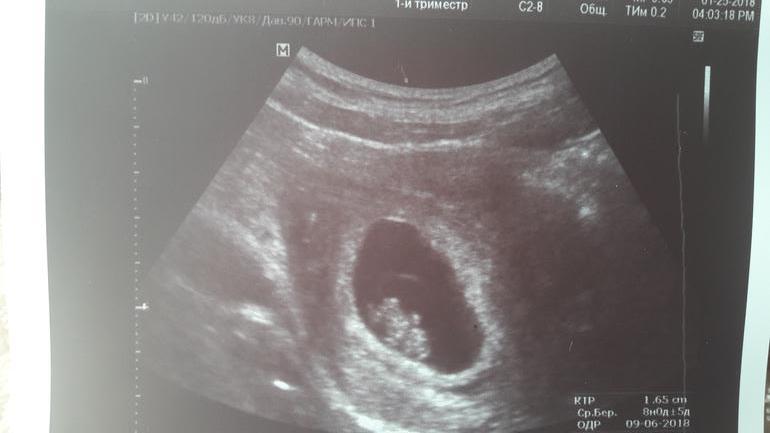

Внеплановое УЗИ.

Пошла внепланово на УЗИ в платную клинику и

Привет,малыш.

Из неприятного:тонус.Меньше нервничать.